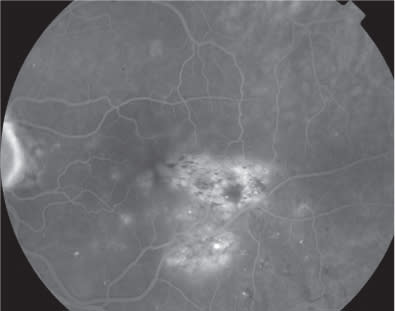

The patient was evaluated one month later, and he complained of a severe visual acuity impairment in the LE, which had occurred a few days before. BCVA was 0.8 in the RE and 0.05 in the LE. Biomicroscopic examination revealed a hyperemic and swollen optic disc, with several retinal hemorrhages. Retina at the posterior pole was pale, with attenuation and sheathing of arterial vessels. FA showed a delayed optic disc and arterial filling with extensive retinal ischemia involving both posterior pole and periphery (Figures 4 and 5). The picture was consistent with the diagnosis of anterior ischemic optic neuropathy associated with retinal arterial occlusion. Carotid doppler ultrasound, electrocardiogram and echocardiogram examinations revealed no alterations.

Figure 5. Composite fluorescein angiography in the early phases showing a delayed optic disc and arterial filling with extensive retinal ischemia involving both posterior pole and periphery.